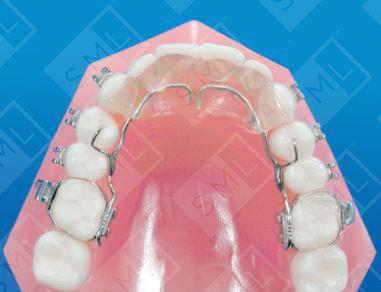

The upper has a simple bite plane that is designed to hold the arches at the ideal vertical relationship. This bite plane is placed on a lingual wire attached to the first molar bands via a vertical removable bracket assembly. Because the upper is to be worn 24 hours per day, the bite plane should be kept to a minimum (to allow for comfort and ease of speech).